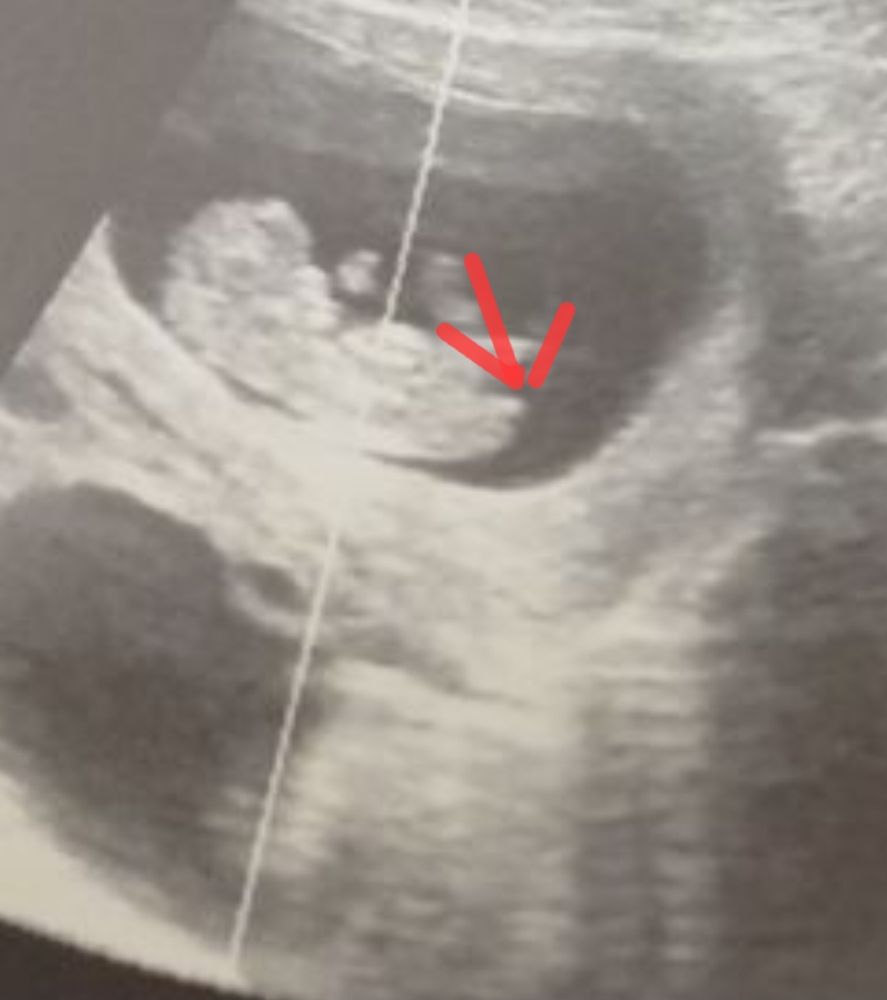

Здравствуйте девочки ,задалась вопросом ..когда виден половой бугорок ?

по узи срок 12,4 (по факту 11,5)

я не вижу никаких бугорков…или фото такие не пойму

Половой бугорок это маленькая белая ровная черточка на узи. У вас не особо видно её, а есть другие фото?

На этом фото и не найдёте. Нужен другой ракурс. И ещё рано. Подождите до 16 нед. На вашем сроке часто ошибаются

Позавчера была на первом скрининге, срок 12.2, врач сказала что между ножек еще гладко всё

Да,тут не особо удачно,но предположу девочку.

Не видно бугорка, ножкой всё прикрыто)